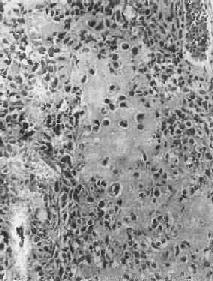

图17-7 硬化性骨肉瘤 股骨干骺端呈梭形肿大,骨干被包埋于中央,周围有清晰的放射状骨梁 骨肉瘤的切面呈多彩状,其外观取决于肿瘤性骨质及软骨的含量以及出血、坏死等继发改变的程度。例如,肿瘤性骨质成分较多时则肉眼观呈黄白色,质地坚硬,有砂粒小点或条纹;如软骨形成明显时则呈半透明状;在肿瘤细胞丰富部位则呈灰红色鱼肉状。 镜下,骨肉瘤由明显间变的梭形或多边形肉瘤细胞组成,细胞大小不等,核形奇异,大而深染,核仁明显,易见病理性核分裂像。肿瘤细胞直接形成肿瘤性类骨组织或骨组织,是诊断骨肉瘤的最重要的组织学依据。所形成的类骨组织或骨组织在不同肿瘤或同一肿瘤的不同部位多少不等。往往可看到肿瘤性骨质发生过程中各阶段的形态,最早期在恶性肿瘤细胞间出现均质红染的胶原样物质,其后红染物质逐渐增多,将肿瘤细胞分隔疏远,构成小梁或片状的肿瘤性类骨组织(图17-8)。类骨组织可伴钙盐沉着,其内的肿瘤细胞固缩变小,形成肿瘤性骨质。骨肉瘤内也可出现肿瘤性软骨(图17-9)。

图17-9 骨肉瘤 骨肉瘤起源于间叶细胞,形态上表现出多方向分化的潜能,而使骨肉瘤的成分较为复杂。根据其主要的分化成分,组织学上可分成几种类型:最常见者为骨母细胞型,以异型骨母细胞为主要成分,细胞呈多边形,较肥硕,核圆、核仁明显,胞浆丰富,伴较多的肿瘤性类骨和骨组织形成;由软骨肉瘤样组织为主要成分者,属软骨母细胞型;以梭形细胞和胶原纤维为主,似纤维肉瘤者为纤维母细胞型;肿瘤内有许多显著扩张的血管腔隙,伴较多破骨细胞型多核巨细胞,甚似动脉瘤性骨囊肿者为血管扩张型,此型十分少见。在同一肿瘤中上述各种类型的成分常混合存在,但以某一类型为主。不论何种类型,都能见到肿瘤细胞直接形成肿瘤性类骨和骨组织,这是区别于其他骨肿瘤的特征。 【临床病理联系】 骨肉瘤最早的症状是局部疼痛,日渐加剧,持续不断,以夜间为明显。发病2~3月后,局部出现肿胀、质地坚硬。患部皮肤紧张,多呈紫铜色,表面静脉曲张。如骨皮质受侵犯时,轻度外伤即可致病理性骨折。 血清碱性磷酸酶的增高是骨肉瘤的唯一重要化验室检查指征,这和瘤组织内碱性磷酸酶的含量增高相一致,约见于半数病例,对骨肉瘤诊断和推测预后有一定价值。 X线检查对骨肉瘤的诊断有重要价值。常见到肿瘤性骨质形成,表现为云絮状或斑块状密度增高的阴影。这类病例在X线诊断时称为硬化型骨肉瘤。少数病例呈溶骨型,病理上主要为软骨母细胞型和纤维母细胞型以骨质破坏为主,呈虫蚀状或大片状骨质破坏,边界模糊。如前所述,X线检查如发现Codman三角或日光放射状阴影,则对骨肉瘤的诊断很有帮助。 骨肉瘤是高度恶性肿瘤,一般生长迅速,预后较差。局部扩展一方面侵犯骨髓腔及骨皮质,并破坏骨膜及周围软组织;另一方面向骨骺蔓延,甚至扩展到关节软骨。极少数病例可越过关节软骨,侵入关节囊,造成关节活动障碍。近年还发现,骨肉瘤在骨内可呈跳跃性转移(skip metastasis),即在与原发瘤同一骨内的另一处形成孤立性转移结节,甚至还可以转移到相邻的骨内,形成孤立结节,约见于1/4的病例,且不易被X线检查发现,因而预后更差。远处转移多经血道到肺,不少病例在发现原发瘤的同时,即已有肺转移。极少数病例可转移到局部淋巴结。 皮质旁骨肉瘤是骨肉瘤的一种特殊亚型。与一般骨肉瘤不同,本瘤发生于骨膜或骨旁的成骨性纤维组织,瘤体的主要部分位于骨的表面。大多生长缓慢,恶性程度较低,预后远较一般骨肉瘤好,其发病年龄比一般骨肉瘤大5~10岁。本瘤好发于股骨下端的后方,其次为股骨上部。瘤体一般较大,边界较清晰,可呈分叶状。早期对骨质侵犯较少,故易于剥离;晚期可破坏骨皮质而侵犯骨髓腔,但远处转移少见。在切面上,靠近骨皮质或骨膜部分质坚实,而瘤体边缘部分较软,为富于瘤细胞部分。瘤体一般不见出血及坏死。镜下,为分化好的骨肉瘤,成骨现象比较明显。在肿瘤性骨小梁间为增生较活跃的纤维组织,间变不明显,形态上似分化好的纤维肉瘤。少数皮质骨肉瘤分化较差,形成骨质较少,与骨内骨肉瘤相似。